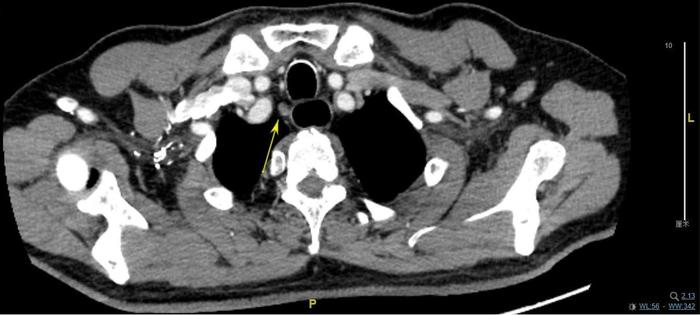

上图,左喉返神经旁淋巴结,7.2毫米,手术切除后病理为良性淋巴结。

上图,右喉返神经旁淋巴结,9×6毫米,手术切除后,病理为良性淋巴结。